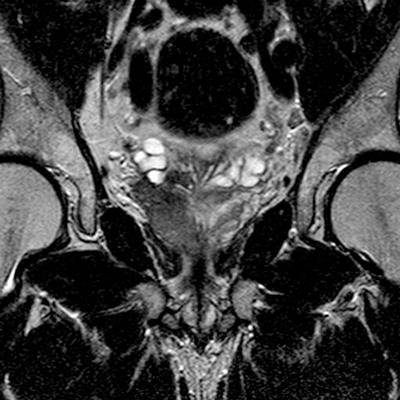

Seminal vesicle involvement (SVI) denotes T3b disease, and is another important prognostic indicator as it is associated with a high rate of treatment failure and lower survival rates [4]. Tumour infiltration of the seminal vesicles appears as a low signal intensity area within the normal high signal intensity fluid of the seminal vesicles on the T2W images [3]. Asymmetry of the seminal vesicles, obliteration of the angle between the base of the prostate and the seminal vesicles, and low-signal intensity within enlarged ejaculatory ducts may also indicate involvement (Figure 6) [2].

Figure 6: Coronal T2 image showing extensive right peripheral zone

tumour with extension into the base of the right seminal vesicle.